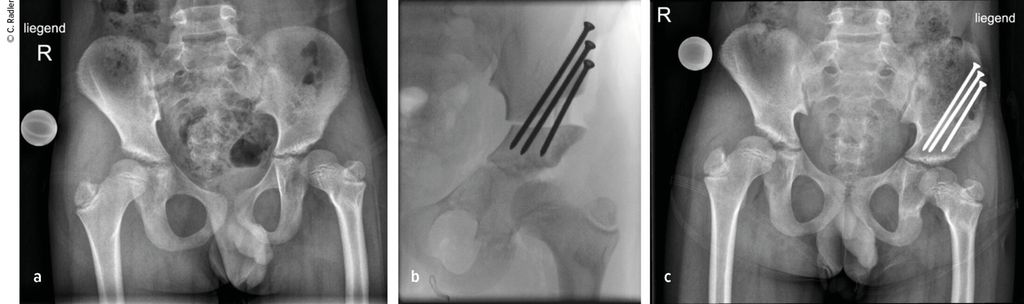

Der Typ 1B ist durch eine verzögerte Ossifikation/Pseudoarthrose subtrochantär oder im Schenkelhalsbereich charakterisiert, wobei auch ein kombinierter Typ mit Schenkelhals und subtrochantär verzögerter Ossifikation vorliegen kann. Klinisch imponiert neben der massiven Verkürzung die Außenrotations- und Beugekontraktur. In diesen Fällen ist eine komplexe Rekonstruktion, bestehend aus mehreren Schritten, erforderlich, die als Super-Hip-Operation subsumiert wird (Abb. 3).

Typ 1B2 und 1B3

Bei den Typen 1B2 und 1B3, also bei Vorliegen einer verzögerten Ossifikation des Schenkelhalses, wird am Endenoch proximal der Klingenplatte BMP 2 über ein Bohrloch eingebracht. Nach Refixation der Rectussehne und Wundverschluss wird ein Becken-Bein-Gips für 4–6 Wochen angelegt. Während die Typen 1B mit entsprechender Erfahrung gut und reproduzierbar rekonstruiert werden können. ist dies beim Typ 2 deutlich schwieriger und mit deutlich mehr Risiko eines Versagens des Verfahrens und entsprechenden Komplikationen verbunden.

Typ 2A

Beim Typ 2A liegt zusätzlich eine fibröse Pseudarthrose zwischen Hüftkopf und Femurschaft vor, wobei die Apophyse des Femurs vorhanden ist. Für die Rekonstruktion muss die Hüftkapsel eröffnet werden und die Anlage des Schenkelhalses im Bereich der Pseudarthrose angefrischt und gegenübergestellt und schließlich mit Cerclagen unter Kompression gesetzt werden. Erst dann können die anderen Schritte der Super-Hip-Operation durchgeführt werden. Weiters ist zum Schutz der instabilen Hüfte ein temporärer Fixateur hüftübergreifend erforderlich.